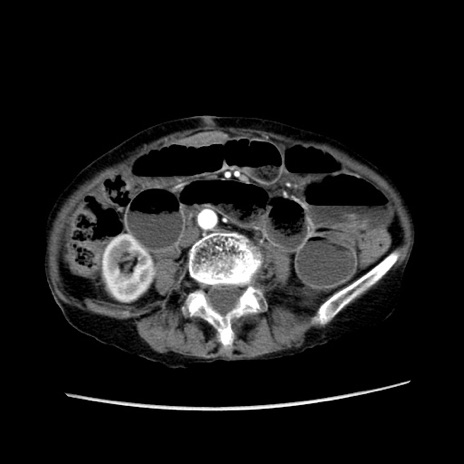

症例25(横断像)

【症例】80歳代女性

【主訴】胸のつかえ感

【現病歴】約9時間前に食後から胸のつかえた感じあり、嘔吐あり、来院。

【既往歴】胃癌(全摘)、胆摘、虫垂炎

【身体所見】心窩部に圧痛あり、反跳痛なし。

【データ】WBC 5700、CRP 0.05